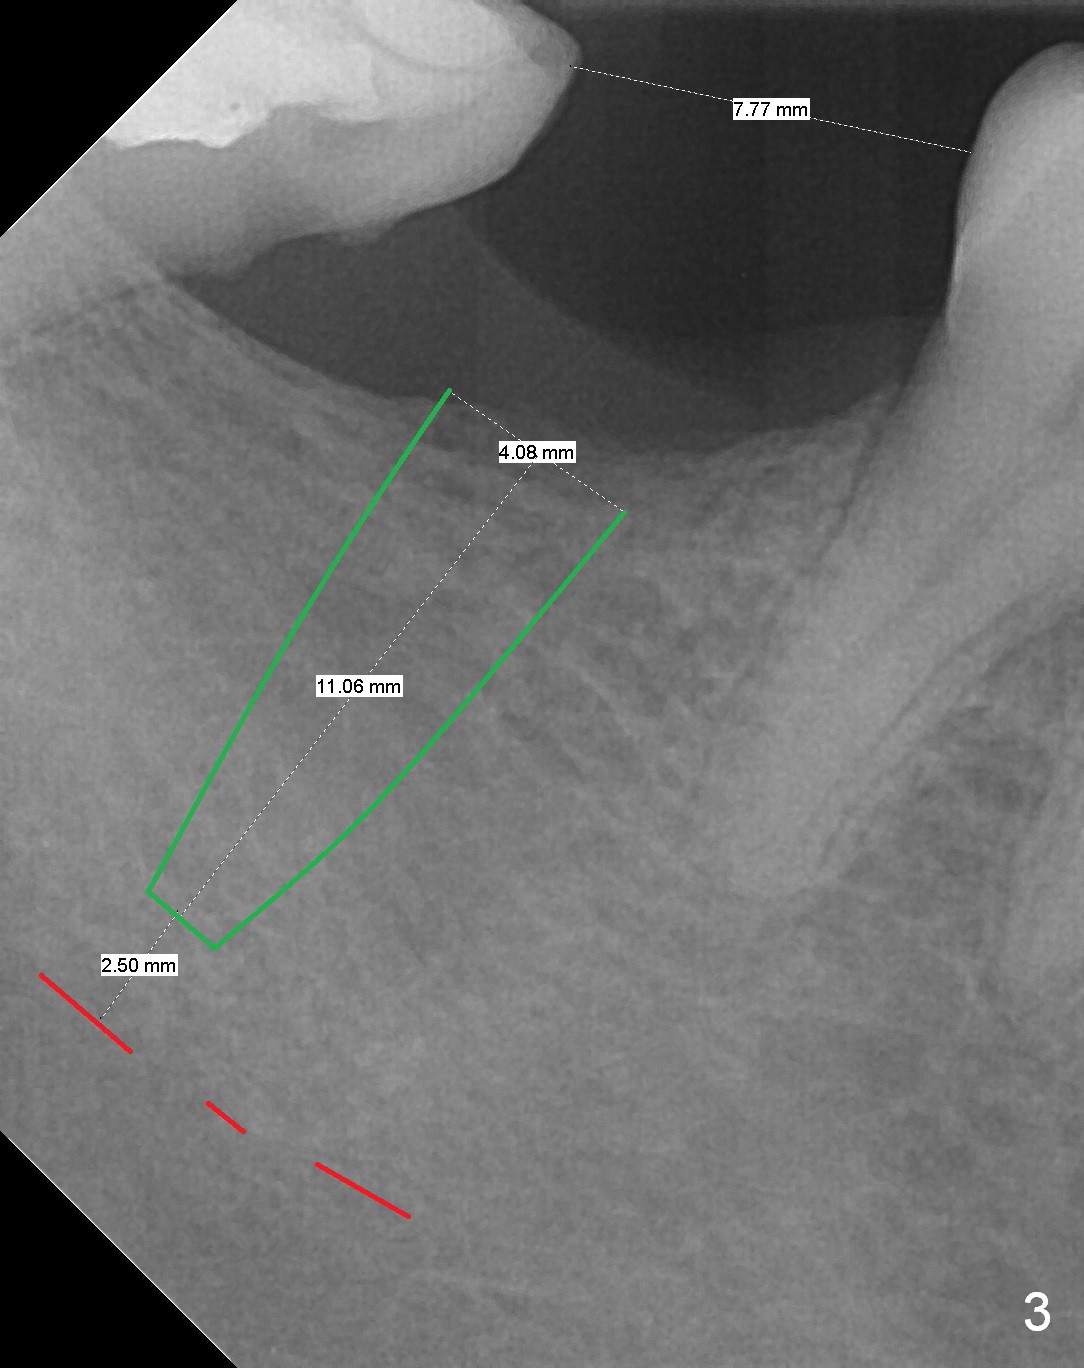

A 39-year-old man presents to office for #19/20 composite redo. After discussion he agrees to restore #31 with implant (Fig.1-3). He worries about bone loss (buccolingually) because of 8-year loss of the tooth. Fortunately the mesiodistal space is less than 8 mm (Fig.3). A 4 mm IBS implant (Titanium V (Bicon as well) stronger (not easily break) than Titatium IV (Tatum, DIO)) should be able to sustain mastication if the tooth #32 is not extracted. After local anesthesia, remove calculus in the mesial surface of #32 (Fig.2 ^). Also prepare for MO composite at #30.